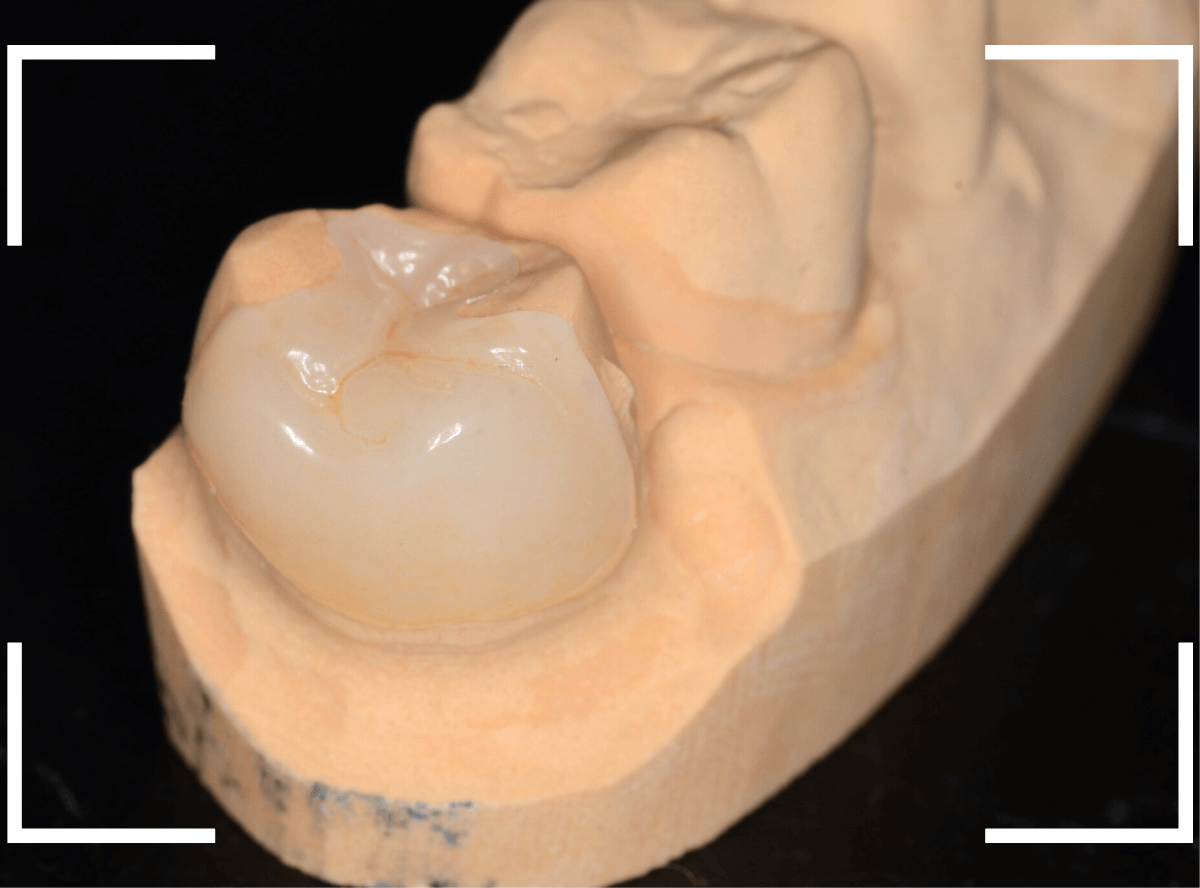

さて、しばらく経過観察した後、症状もありませんでしたので、型どりをして最終修復に入ります。

「良い素材で治療をしたい」という患者さんのご希望でしたので、ジルコニア・インレーで治療をする事になりました。

模型上で精密に製作します。

set後の写真です。

なんとか審美性も確保した状態で治療を終われました。

| 治療回数 | 3回 |

| 治療期間 | 3週間 |

| 費用 | ジルコニア・インレー (70,000円) +保険治療費用(虫歯の治療費用など) |

| メリット | 経年劣化で腐食しない 清掃性が高く、プラークや歯石がたまりにくい |

| デメリット | かみ合わせの強い方はまれに割れる事がある 保険診療に比べて高価 |

2024年6月現在

今回は、できるだけ良い素材での治療をご希望されましたので、ジルコニア・インレーでの治療となりました。

型を取った製作した模型上でジルコニア・インレーを製作します。

お口の中でsetしたところです。

ほとんど調整する事もなく、ピッタリと合わせる事ができました。